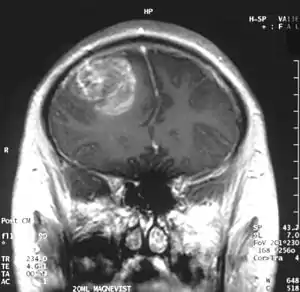

| Coronal MRI with contrast of a glioblastoma WHO grade IV in a 15-year-old male. | |